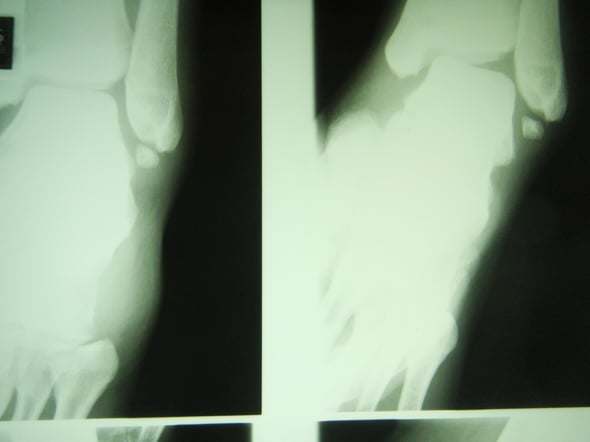

〇リスフラン脱臼骨折

折れた骨と関節をビスで固定する手術をしました。

手術は成功していますが、その後のギプスが足に合わず圧迫を受けていました。

夜も眠れないほどの痛みは処置後の悪循環によるものと思われます。

皆さんは骨折してるのだから痛いのは当り前だと思い込んでいますが、何週も経過して夜眠れないほどの痛みは悪循環そのものです。

適切な処置が行われていれば苦しむことはありません。